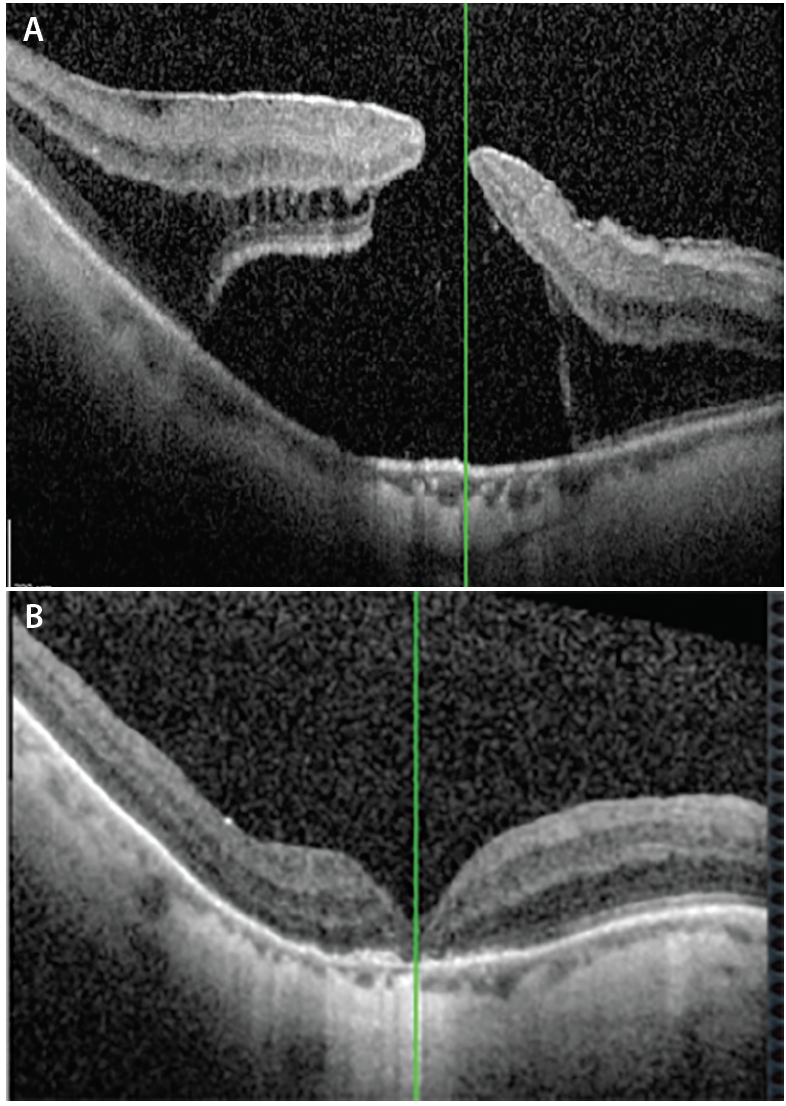

Figure. OCT of localized retinal detachment associated with macular hole in a 60-year-old woman with -10 D. VA was counting fingers (A). OCT 6 months after vitrectomy with inverted flap and autologous blood technique. Macular hole closed and VA improved to 20/200 (B).

Excellent anatomic closure rates are seen with this technique as well as visual improvements, although the visual outcomes depend on the size of the hole, atrophy (in myopic patients), duration of retinal detachment (in holes associated with myopic detachments), and RPE status (Figure).